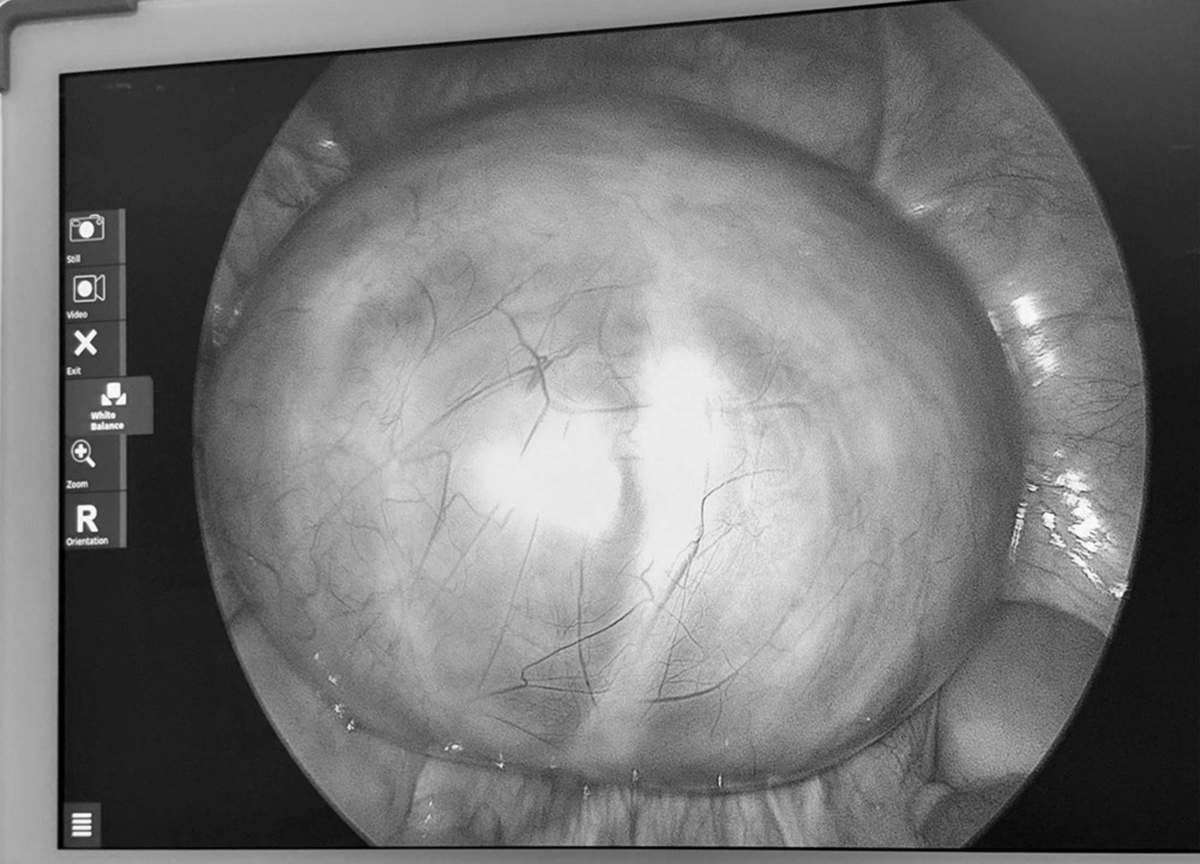

Tại viện qua siêu âm, các bác sĩ phát hiện buồng trứng trái có khối u lớn khoảng 14cm, cấu trúc nhiều vách. Sau hội chẩn, ê-kíp khoa Phụ sản đã tiến hành phẫu thuật vào ngày 3/4. Ca mổ diễn ra thuận lợi, khối u được bóc tách hoàn toàn, đồng thời bảo tồn tối đa chức năng sinh sản cho người bệnh.